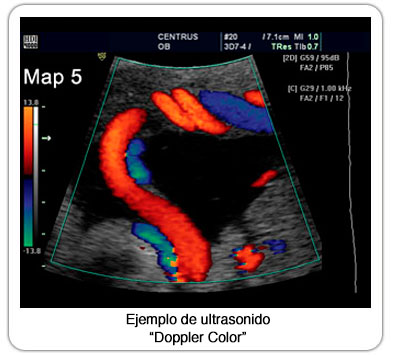

Todos nuestros ultrasonidos doppler cuentan con transductores que tienen la posibilidad del Doppler Color, que tiene aplicación primordial en patología de arterias y venas, aplicables en el sistema carotídeo y sistema venoso profundo de extremidades.

También el Doppler Color es de ayuda importante para distinguir masas benignas de malignas llegando a detectar baja velocidad de flujo, shunts a-v y vasos nutricios, características de tejido de neoangiogénesis o vasos neoformados.

El ultrasonido es básico en la evaluación de órganos pre y post trasplante. En general el Doppler Color se utiliza como contraste vascular en los diferentes órganos de la economía corporal para su óptima localización y certeza diagnóstica.